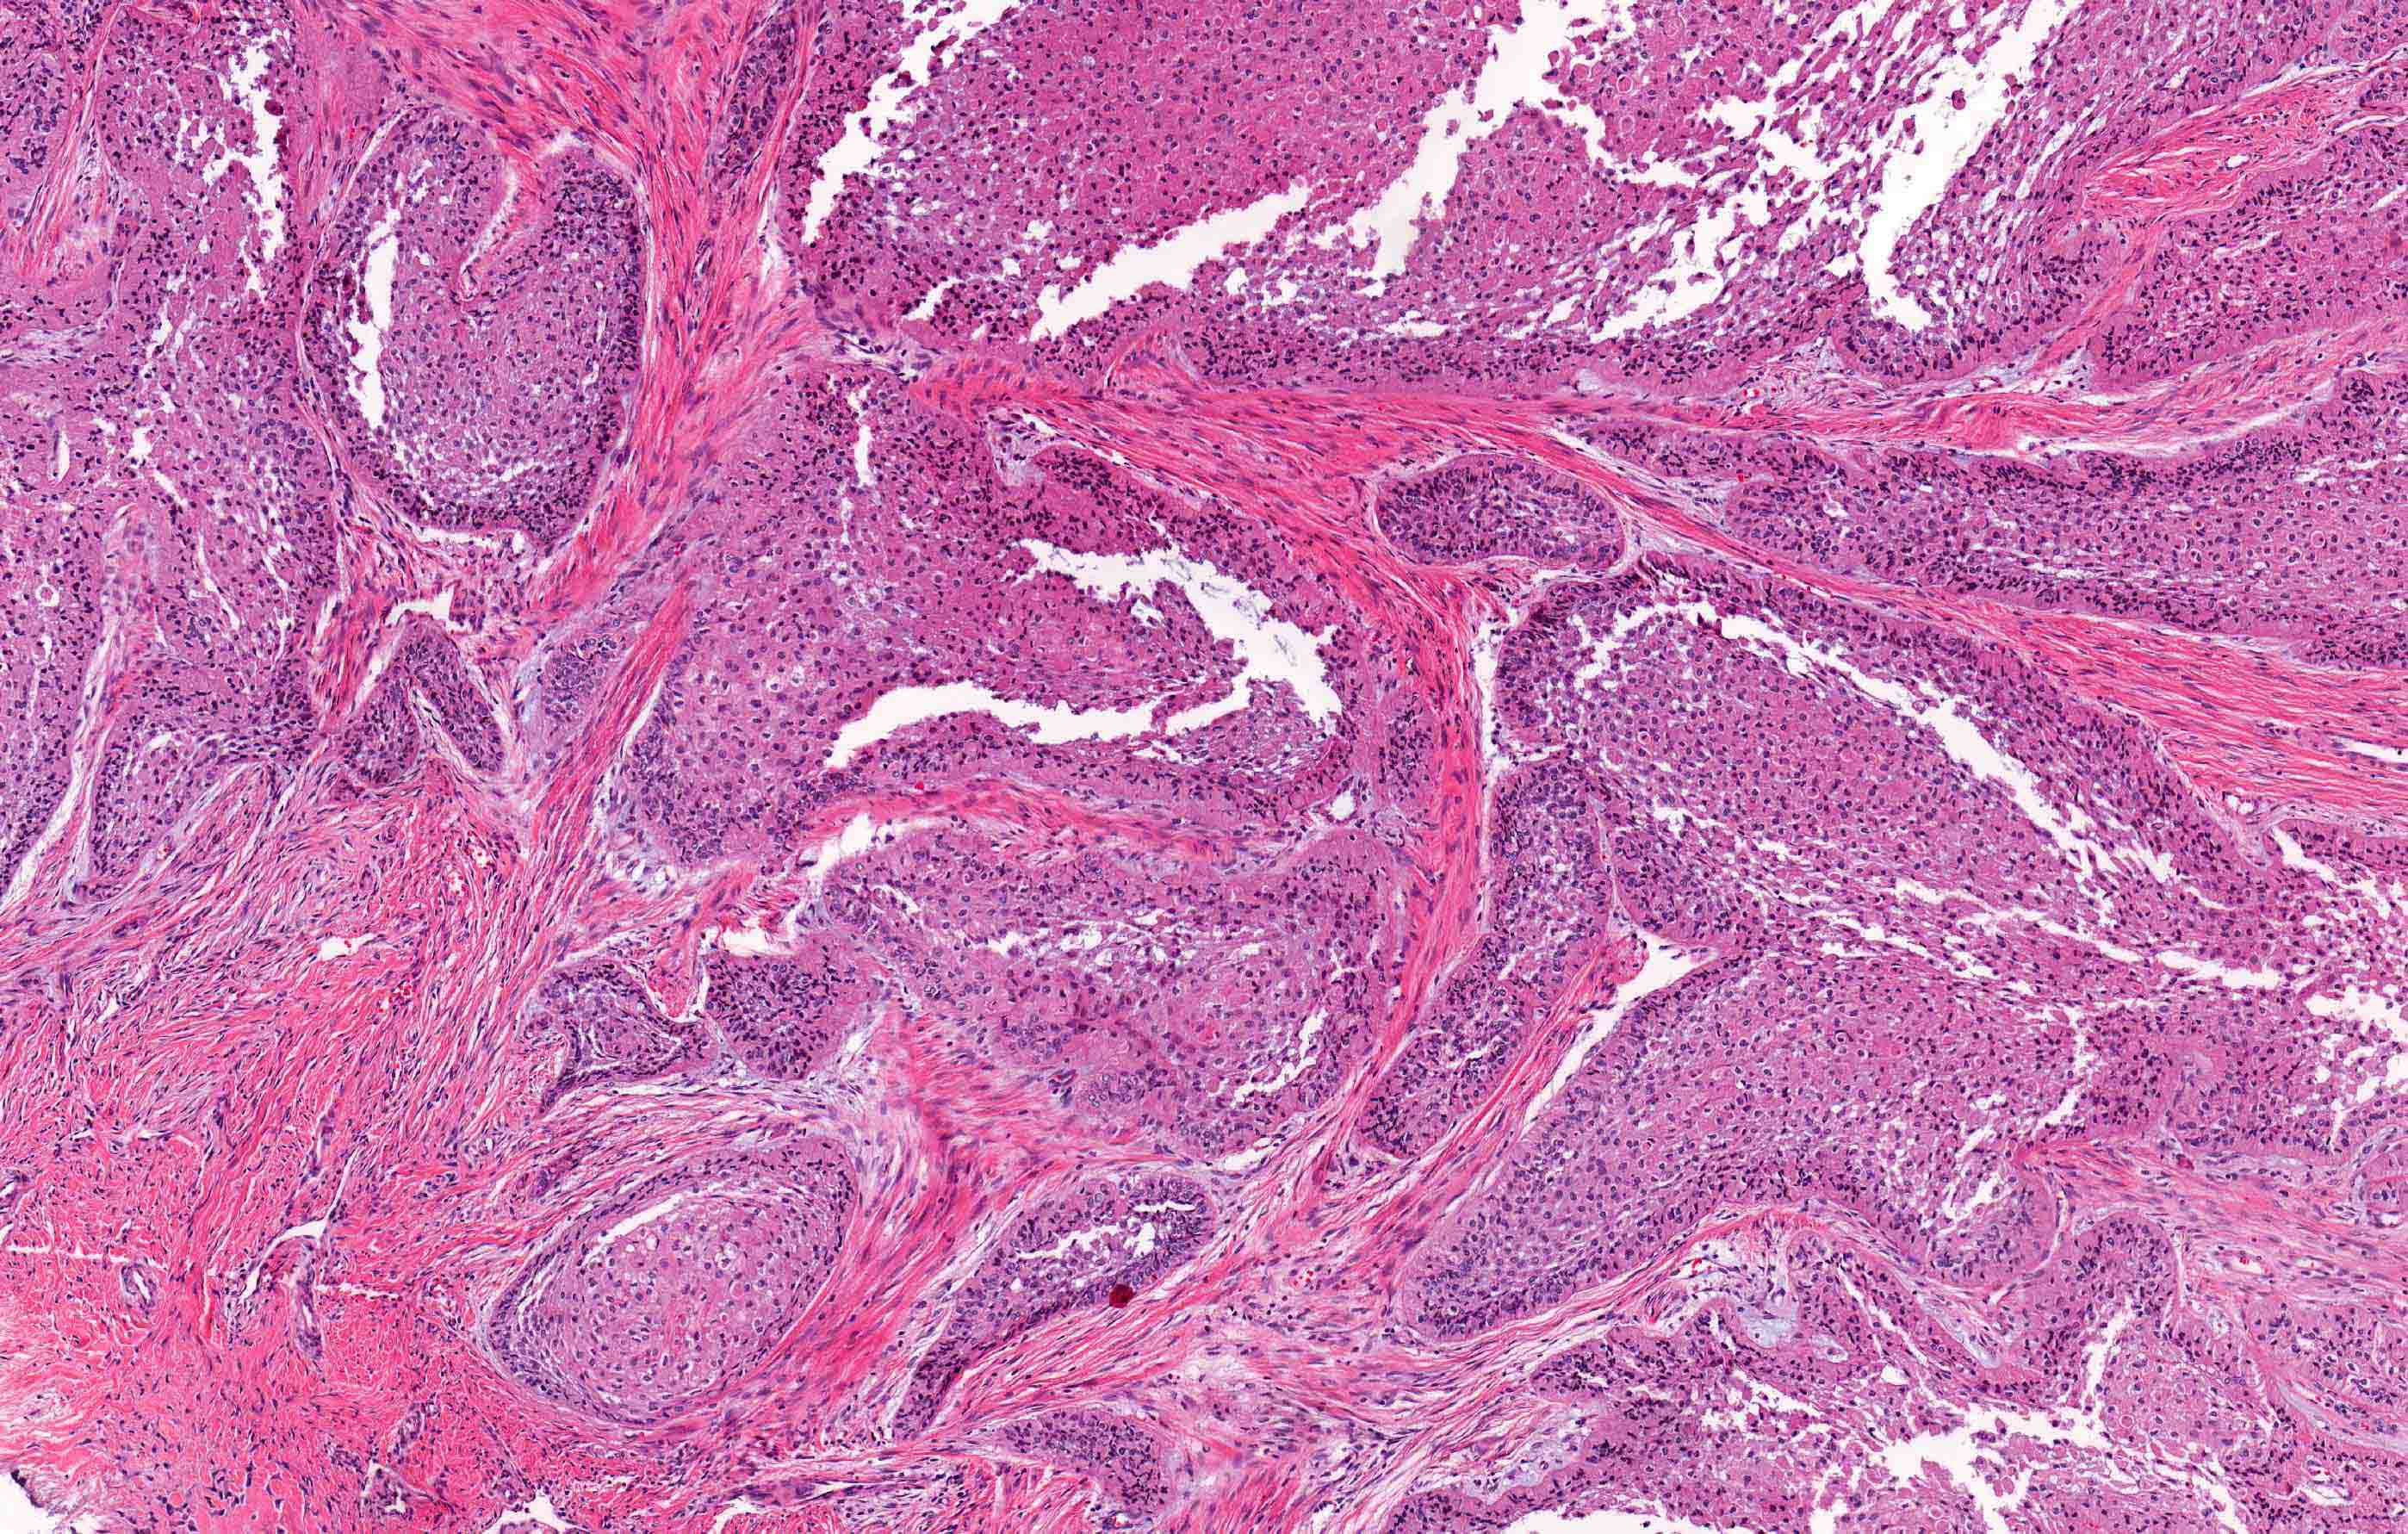

- Ameloblastoma, conventional type has at least 6 histopathological patterns

- Single patterns may predominate within a given lesion, often mixed with 1 or more patterns

- Follicular: most common subtype; islands of odontogenic epithelium in fibrous connective tissue; may be cystic; classic peripheral palisading and stellate reticulum-like areas

- Plexiform: cords and sheets of anastomosing odontogenic epithelial cells; classic peripheral palisading and reverse polarity not always obvious

- Desmoplastic: compressed and angular islands of epithelial tumor cells with dense moderately cellular fibrous connective tissue or collagenous stroma; the formation of metaplastic bone trabeculae is also described

Contributed by Kelly Magliocca, D.D.S., M.P.H. and Anne C. McLean-Holden, D.M.D., M.S.